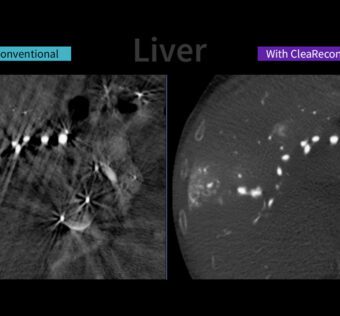

Healthcare IT news - (Thursday May 15, 2025) A pair of recent announcements from the U.S. Department of Health and Human Services show agencies working to help providers and payers reduce their data exchange burdens and enable Medicare enrollees to better manage their… ![]() GE HealthCare Launches AI-Powered CleaRecon DL to Enhance CBCT Image Quality in Interventional Procedures

HIT Consultant - (Thursday May 15, 2025) Source Credit: GE Healthcare What You Should Know: – GE HealthCare today announced the launch of CleaRecon DL, an innovative technology driven by a deep-learning algorithm, designed to significantly improve the quality of cone-beam computed tomography… |